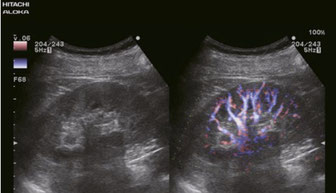

eFLOW

eFLOW ist ein hochauflösender Modus zur Darstellung des Blutflusses mit einer drastisch verbesserten räumlichen und zeitlichen Auflösung. Dies versetzt den Untersuchenden in die Lage, feine Blutgefäße, wie beispielsweise in einem Tumor, präzise abzubilden und abzugrenzen.